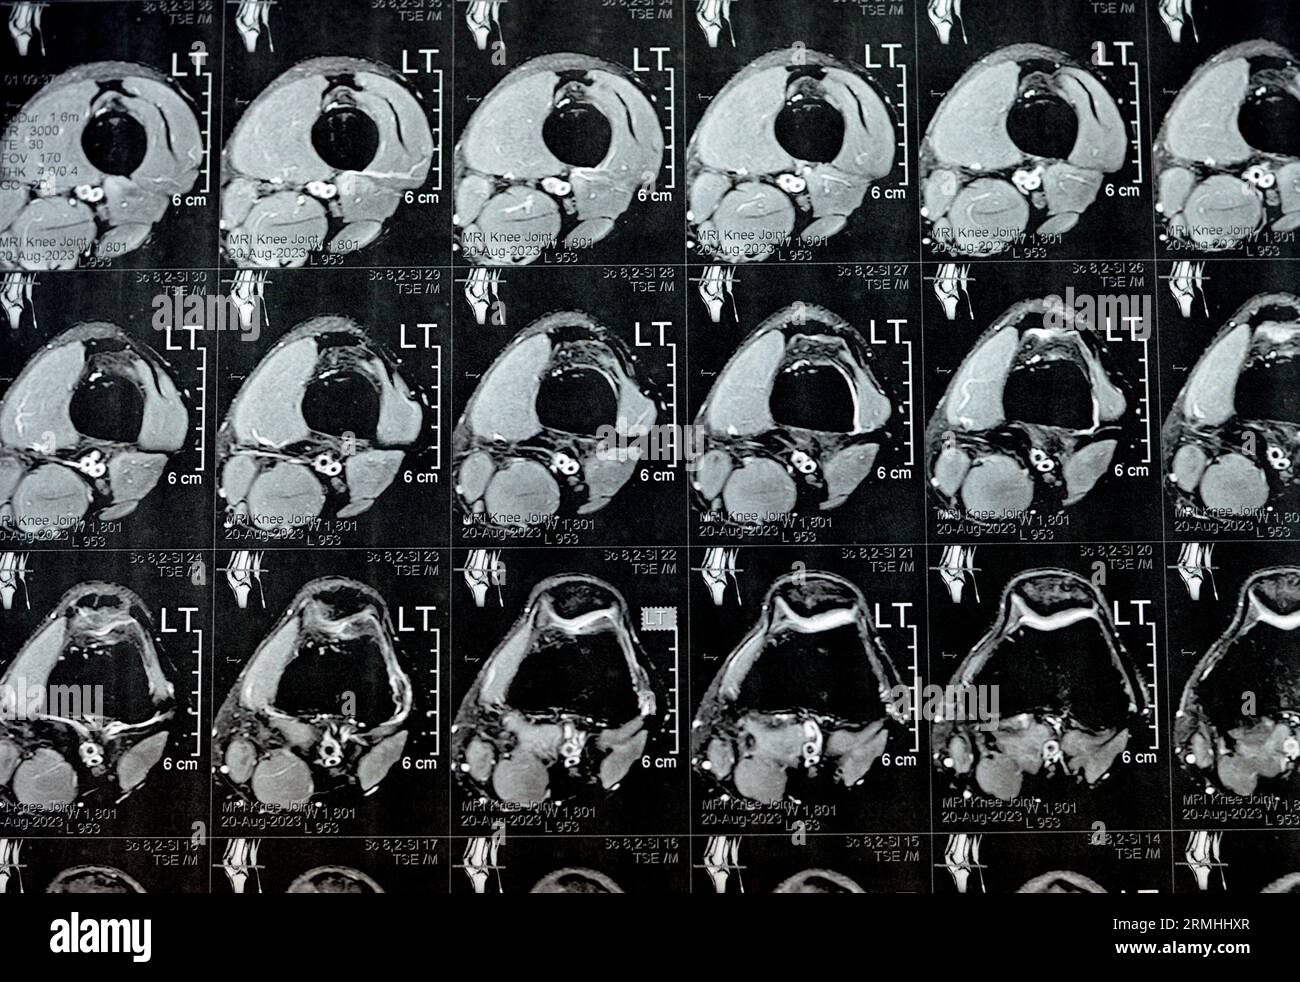

MRI of left knee joint showing minimal joint effusion, PHMM Posterior Anterior Horn Disease Mri Incomplete spinal cord syndromes are reviewed, with descriptions of the relevant spinal cord anatomy and common causes of these syndromes and with emphasis on the correlation of anatomic and imaging findings with clinical manifestations. Emg/ncs, serum and urine electrophoresis,. Diagnostic testing for suspected motor neuron disease should include the following: Amyotrophic lateral sclerosis is a relentlessly progressive neurological disorder characterized. Anterior Horn Disease Mri.

MRI of Left Knee Joint Showing Minimal Joint Effusion, PHMM Posterior Anterior Horn Disease Mri Incomplete spinal cord syndromes are reviewed, with descriptions of the relevant spinal cord anatomy and common causes of these syndromes and with emphasis on the correlation of anatomic and imaging findings with clinical manifestations. The electromyography, nerve conduction studies, mri of the. Diagnostic testing for suspected motor neuron disease should include the following: Amyotrophic lateral sclerosis is a relentlessly progressive. Anterior Horn Disease Mri.

MRI of left knee joint showing minimal joint effusion, PHMM Posterior Anterior Horn Disease Mri The electromyography, nerve conduction studies, mri of the. Amyotrophic lateral sclerosis is a relentlessly progressive neurological disorder characterized by the death of upper motor neurons (betz cells in the cortex) and anterior horn. Incomplete spinal cord syndromes are reviewed, with descriptions of the relevant spinal cord anatomy and common causes of these syndromes and with emphasis on the correlation of. Anterior Horn Disease Mri.

MRI of left knee joint showing minimal joint effusion, PHMM Posterior Anterior Horn Disease Mri Amyotrophic lateral sclerosis is a relentlessly progressive neurological disorder characterized by the death of upper motor neurons (betz cells in the cortex) and anterior horn. Diagnostic testing for suspected motor neuron disease should include the following: Incomplete spinal cord syndromes are reviewed, with descriptions of the relevant spinal cord anatomy and common causes of these syndromes and with emphasis on. Anterior Horn Disease Mri.

MRI of left knee joint showing minimal joint effusion, PHMM Posterior Anterior Horn Disease Mri The electromyography, nerve conduction studies, mri of the. Flexion cervical mr imaging is a very useful investigation in diagnosing hirayama disease. Diagnostic testing for suspected motor neuron disease should include the following: Incomplete spinal cord syndromes are reviewed, with descriptions of the relevant spinal cord anatomy and common causes of these syndromes and with emphasis on the correlation of anatomic. Anterior Horn Disease Mri.

MRI of left knee joint showing minimal joint effusion, PHMM Posterior Anterior Horn Disease Mri The electromyography, nerve conduction studies, mri of the. Incomplete spinal cord syndromes are reviewed, with descriptions of the relevant spinal cord anatomy and common causes of these syndromes and with emphasis on the correlation of anatomic and imaging findings with clinical manifestations. Emg/ncs, serum and urine electrophoresis,. Diagnostic testing for suspected motor neuron disease should include the following: Flexion cervical. Anterior Horn Disease Mri.

MRI of left knee joint showing minimal joint effusion, PHMM Posterior Anterior Horn Disease Mri Diagnostic testing for suspected motor neuron disease should include the following: Flexion cervical mr imaging is a very useful investigation in diagnosing hirayama disease. The electromyography, nerve conduction studies, mri of the. Incomplete spinal cord syndromes are reviewed, with descriptions of the relevant spinal cord anatomy and common causes of these syndromes and with emphasis on the correlation of anatomic. Anterior Horn Disease Mri.

MRI of left knee joint showing minimal joint effusion, PHMM Posterior Anterior Horn Disease Mri Incomplete spinal cord syndromes are reviewed, with descriptions of the relevant spinal cord anatomy and common causes of these syndromes and with emphasis on the correlation of anatomic and imaging findings with clinical manifestations. The electromyography, nerve conduction studies, mri of the. Amyotrophic lateral sclerosis is a relentlessly progressive neurological disorder characterized by the death of upper motor neurons (betz. Anterior Horn Disease Mri.